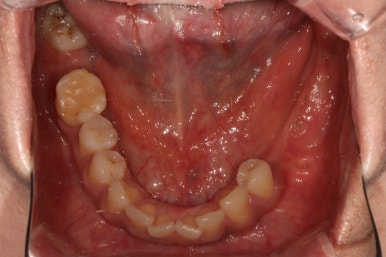

아래턱 교합면입니다.

역시나 충치가 심했던 사랑니는 제거되었고, 비어있던 자리는 임플란트로 대체되었습니다.

색깔과 모양이 상당히 마음에 드는 완성도입니다.

이제 진짜.. 자연치라고 해도 잘 모를 정도로 치과치료의 완성도가 높아졌습니다.